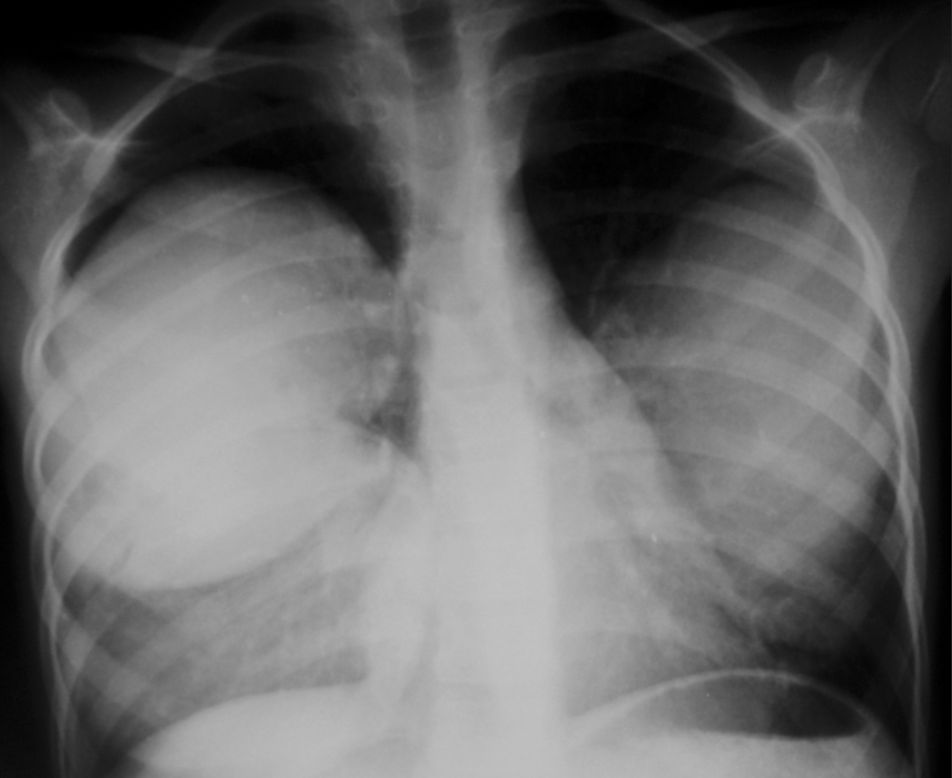

Chest X-ray revealed two nodular opacities (fluid density lesions) in right lung and one in left lung.

Thorax CT revealed two cysts in right lower and medium lobe of lung and one cyst in lingual lobe of left lung. The diagnosis of hydatid cysts was confirmed at surgery.